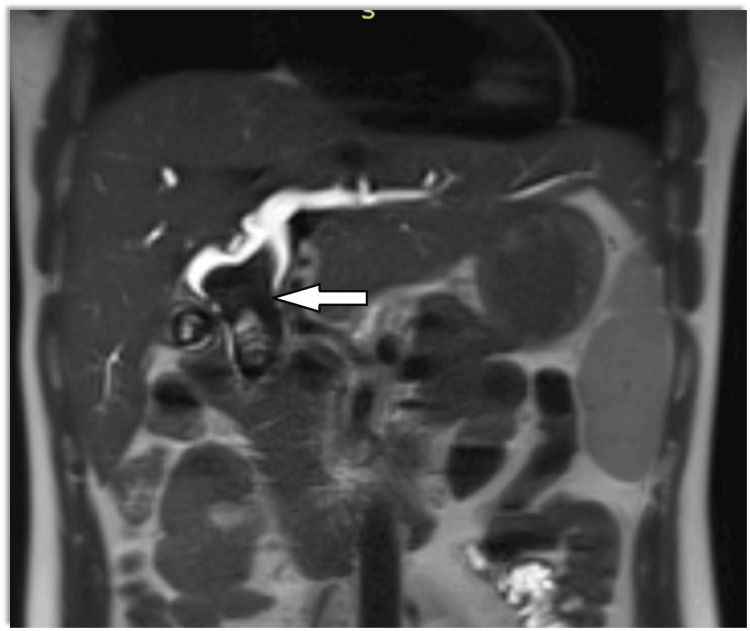

Magnetic resonance cholangiopancreatography (MRCP) showed dilatation of bi-lobar intrahepatic biliary radical (IHBR) with dilatated CBD large T2 hypointense and T1 (Figure 1), hyperintense calculus is seen, occupying dilated CBD and common hepatic duct (CHD). It extends into the left hepatic duct (LHD) and right hepatic duct (RHD), with the possibility of type 1c choledocholithiasis with cystolithiasis, and hepatolithiasis with cholelithiasis (Figures 2, 3).